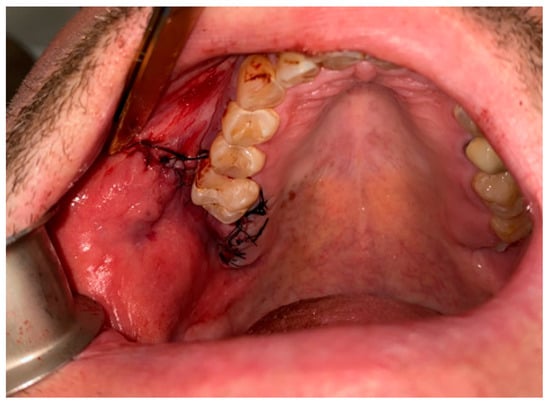

Figure 6. Bichat fat pad mobilization to cover the bone defect and close the oro-antral communication.

Figure 8. Proper suturing of bone defect and closure of the communication between the oral cavity and right maxillary sinus.